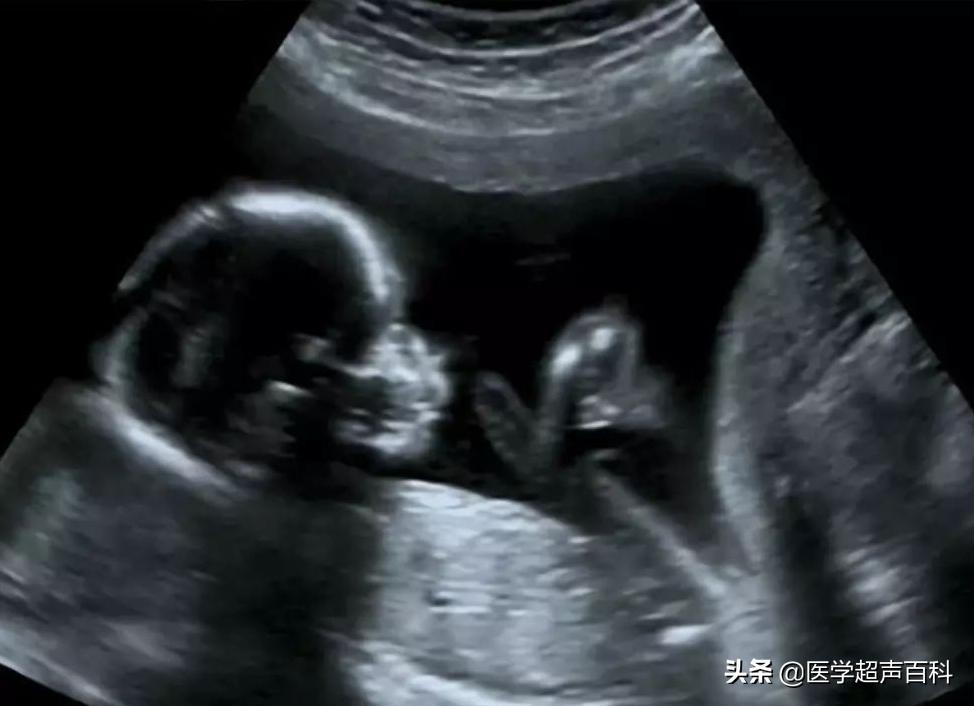

答:B超是产前检查的一个项目,怀孕5周就可以开始做B超检查了,此时通过B超,可以观察妊娠部位是否正常(排除宫外孕),胚胎是否存活。在怀孕的第13周之后,B超可以清晰地显示出胎儿的头颅、躯干、心、肺、肝、脾、胃、肾、膀胱等器官和四肢骨骼的情况等,通过测量所得的数据,估计胎儿发育情况,还能确定有胎位及胎盘位置,评价胎盘功能,选择分娩方式。

四维彩超能够多方位、多角度地观察准妈妈腹内胎儿的生长发育情况,为早期诊断胎儿先天性体表畸形等疾病,提供更正确的依据。比如可以及时发现唇裂、脊柱裂,大脑、肾、心脏、骨骼发育不良等等异常情况,以便尽早进行治疗,提高优生的几率。